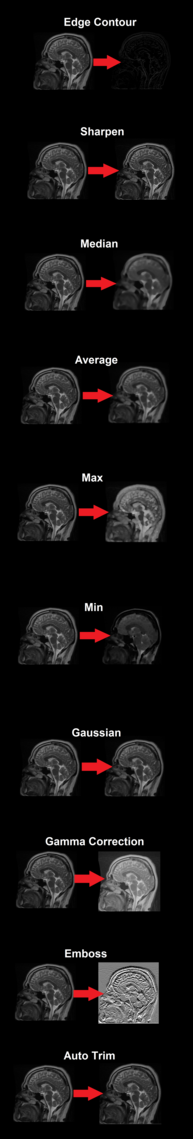

Examples of the different image filter options available:

Edge contour

Emphasizes image points that have a significant intensity difference between pixels

Sharpen

Emphasizes the edges of the image

Median

Removes noise from an image

Average

Max

Removes negative outlier noise

Min

Removes positive outlier noise

Gaussian

Blurs the image

Gamma correction

Controls the overall brightness of an image

Emboss

Indicates the rate of color change

Autotrim

Removes the extra blank space on the side of the image